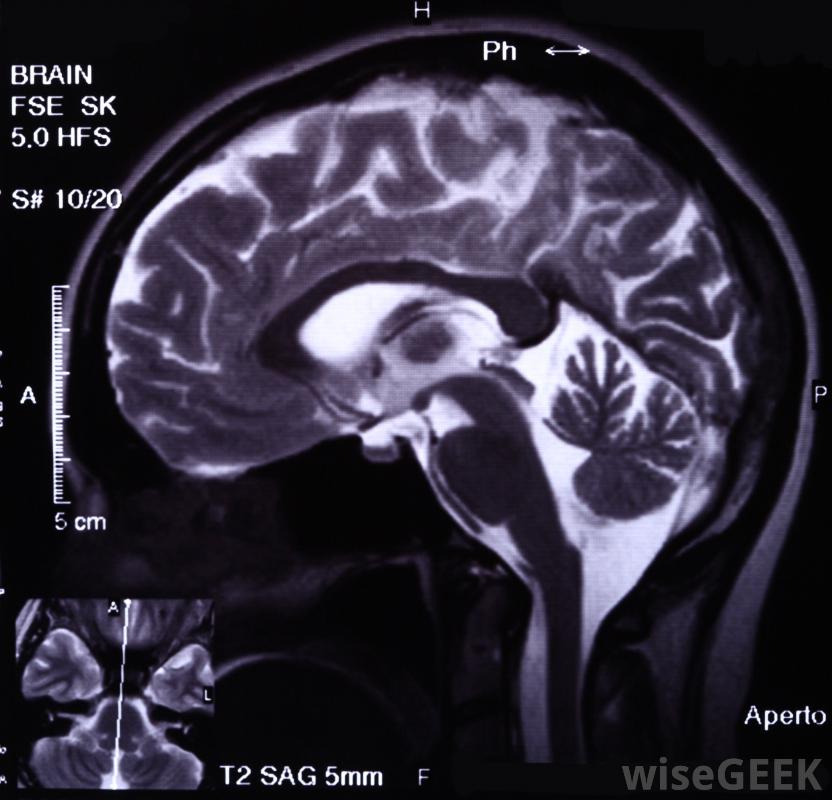

癲癇發作的病理生理學是什么(Pathophysiology of Seizures)?

當大腦的某一部分過度興奮或大腦中的神經開始以不正常的方式一起工作時,就會發生癲癇發作。癲癇發作可能發生在大腦中因先天缺陷或遺傳疾病而畸形的區域,或因感染、傷害、腫瘤、中風而中斷的區域,或氧合不足。癲癇發作的病理生理學是由于刺激和抑制神經細胞的力之間突然失衡,從而使興奮性的力量占上風。這種電信號隨后傳播到周圍的正常腦細胞,在短時間內癲癇發作持續或反復發作,隨著神經細胞死亡,瘢痕組織形成,未來癲癇發作的風險增加,CT掃描可以用來調查病人癲癇發作的原因放電之間的神經細胞通常在內部帶有負電荷,這是由于正電荷的鈉離子從細胞中主動泵出。神經細胞的放電或放電會使負電荷突然波動到正電荷,因為離子通道進入細胞,而正離子如鈉離子,鉀和鈣流入細胞。興奮性和抑制性控制機制都起作用,允許適當的放電和防止細胞的不適當的興奮。癲癇的病理生理學可能是由于神經細胞的興奮性增加,神經細胞的抑制性降低,或兩者的影響的結合大多數癲癇發作是由大腦的電異常引起的。通常在神經細胞著火后,抑制作用阻止神經元的第二次放電,直到神經元的內部電荷恢復到靜止狀態。γ-氨基丁酸(GABA)是大腦中主要的抑制化學物質。GABA為帶負電荷的氯離子涌入興奮的神經元打開了通道,大多數抗癲癇藥物通過增加氯離子通道開放的頻率或增加通道開放的持續時間來降低癲癇的病理生理學。當細胞中釋放GABA或受體的細胞受到破壞時對于GABA,氯離子通道不能打開和調節神經細胞的興奮性。癲癇發作可能需要緊急醫療對癲癇的病理生理學同樣重要的是導致神經元興奮性增強的機制,谷氨酸鹽是大腦中主要的興奮性化學介質,它與打開鈉、鉀和鈣進入細胞通道的受體結合一些遺傳性癲癇發作表現為谷氨酸受體過度頻繁或持續激活,增加了大腦的興奮性和癲癇活動的可能性。此外,電活動沿著大腦分層部分在細胞間連續傳播,一種非化學形式的繁殖,不受抑制機制的調節。嚴重脫水可能導致癲癇發作癲癇的病理生理學治療不僅針對涉及神經細胞離子通道的分子異常,還針對大腦中興奮的非化學擴散,打開抑制性氯離子通道。苯妥英鈉或苯妥英鈉通過關閉進入神經細胞的鈉通道來防止神經元的重復放電。在反復發作管理不善的情況下,氟烷可以阻止神經沖動的非化學傳遞。此外,胰島素和類固醇改變谷氨酸受體的功能,抑制大腦的興奮性。使用非法藥物會增加個體癲癇發作的風險長時間高燒可能導致嬰兒癲癇發作。腦部嚴重創傷可能導致癲癇發作。